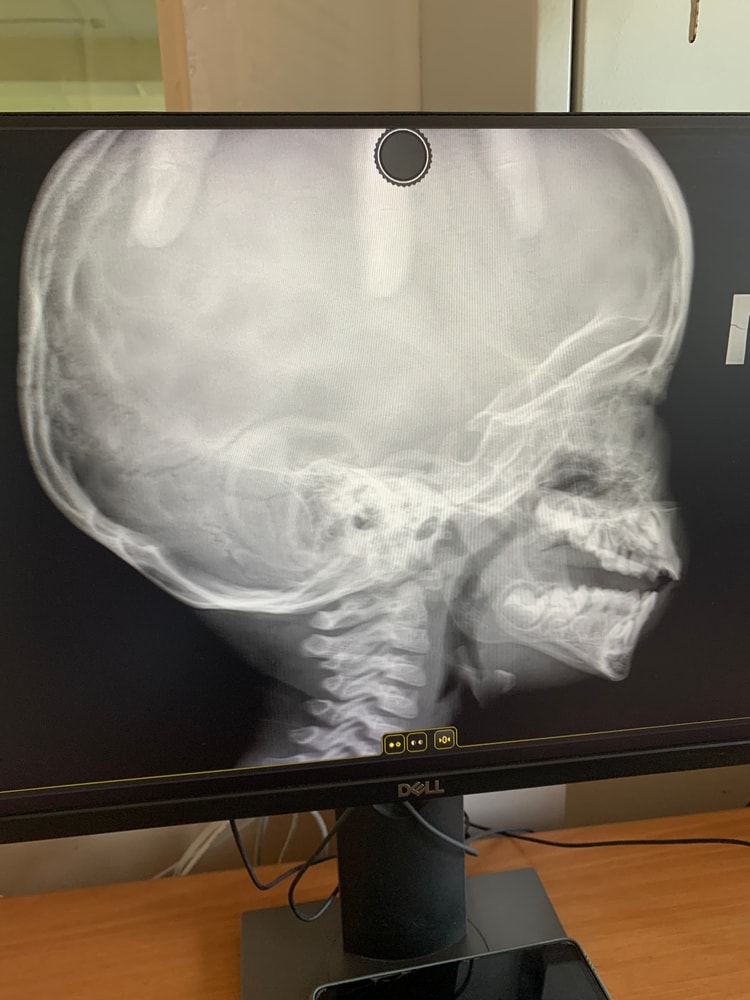

Сын две недели сопливил всеми цветами радуги, кашлял. Врач настояла на снимке, с целью проверить аденоиды. Да только, насколько я знаю, делать надо с открытым ртом. Но в кабинете мне сказали, что делают всем обычно и рот открывать не нужно.

Снимок показала двум врачам. Один говорит, что 1/2 степень. Другой сказал, что это уже 3 и, скорее всего, нужно будет удалять. Сыну 2.4, ну рано же 😫 Дочери удаляли в 3.11, но там уже на слух стало влиять.

Кто разбирается, какая тут степень вообще? И удаляют ли таким малышам аденоиды?